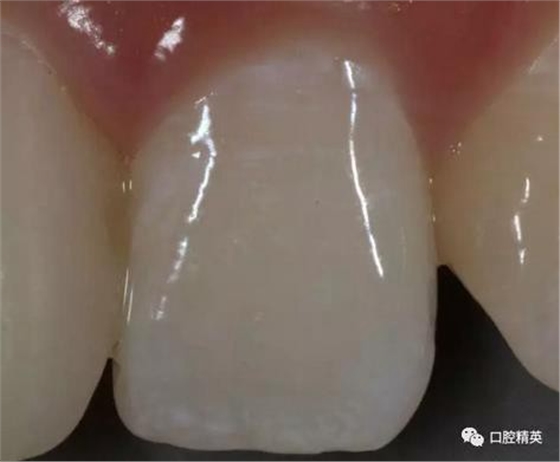

比色,記錄鄰牙顏色細(xì)節(jié)

修復(fù)體展示

口內(nèi)正側(cè)位及切端特寫(xiě)